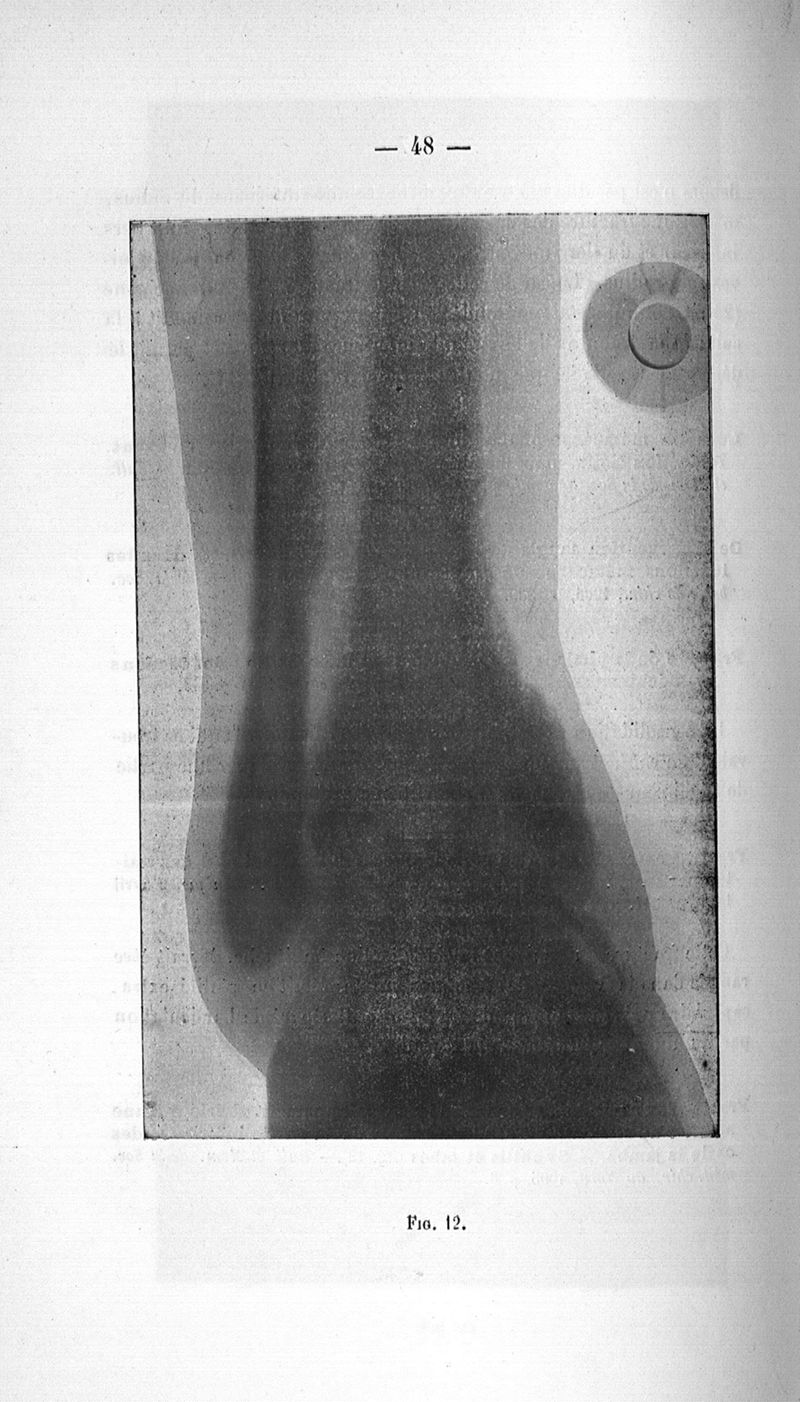

Vanverts, Julien Louis Joseph.

Paris, G. Steinheil, 1907.